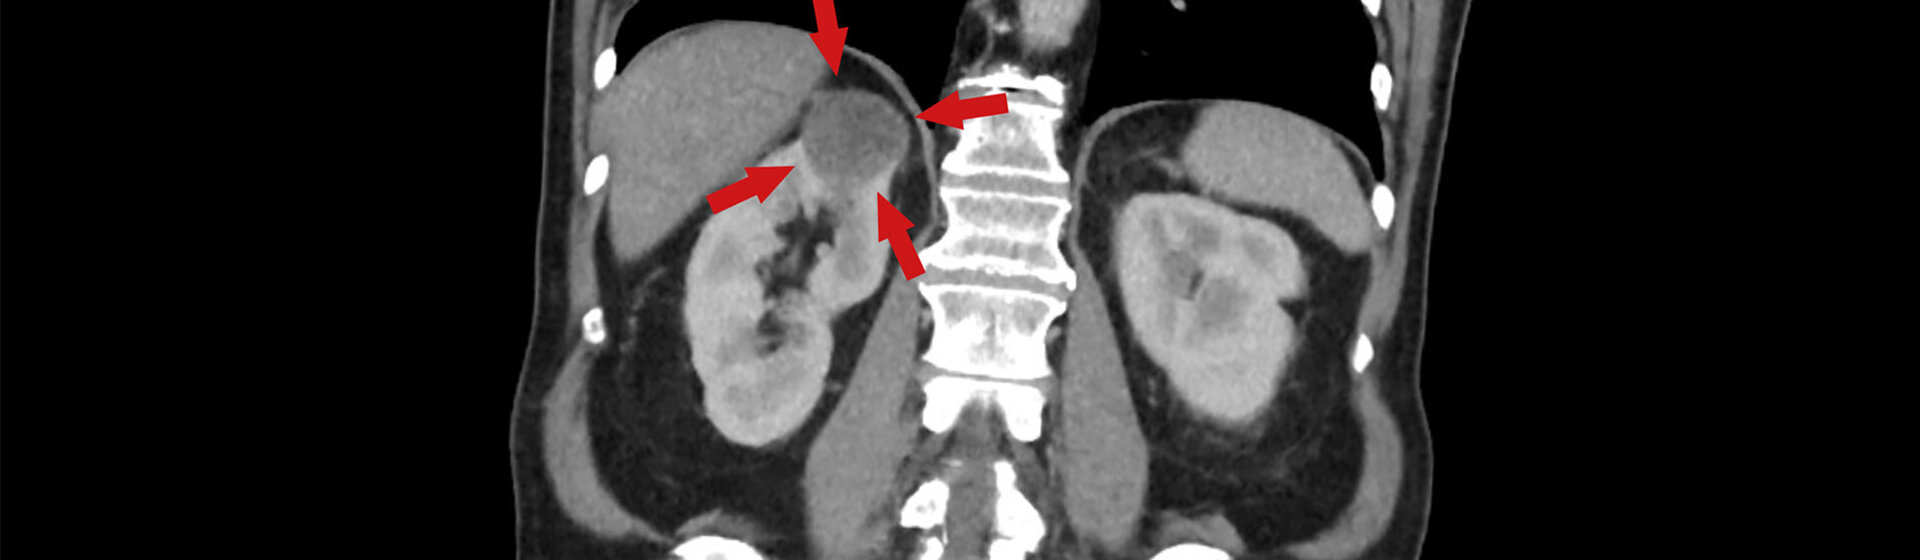

Nierentumor

Nierentumore verursachen erst spät Symptome. Meist werden sie heute

durch eine Ultraschalluntersuchung mehr oder weniger zufällig entdeckt.

Die operative Entfernung des Tumors ist auch heute noch die einzige

kurative (heilende) Behandlungsform.